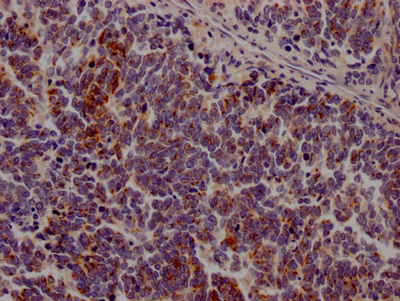

IHC image of CSB-RA206737A0HU diluted at 1:100 and staining in paraffin-embedded human lung cancer performed on a Leica BondTM system. After dewaxing and hydration, antigen retrieval was mediated by high pressure in a citrate buffer (pH 6.0). Section was blocked with 10% normal goat serum 30min at RT. Then primary antibody (1% BSA) was incubated at 4℃ overnight. The primary is detected by a Goat anti-rabbit IgG polymer labeled by HRP and visualized using 0.05% DAB.